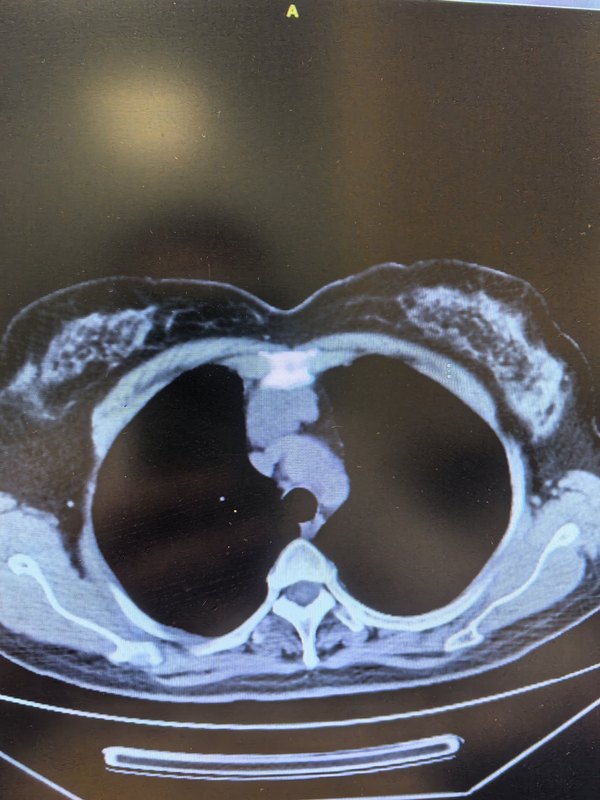

患者年輕女性,因體檢發(fā)現前縱隔巨大腫物,當地醫(yī)院無法手術,經多方咨詢來我科行行微創(chuàng)手術治療。充分完善術前準備,經過1.5h胸腔鏡手術順利完整切除病灶,術后3天恢復出院。術后病理提示胸腺囊腫??v隔囊腫為良性病變,無明顯癥狀不易發(fā)現,多為體檢發(fā)現。手術方式選擇多樣,經劍突下行縱隔占位切除已被證實安全可行,術后患者疼痛感、肺部感染、住院時間也得到減少。完整切除巨大縱隔囊腫